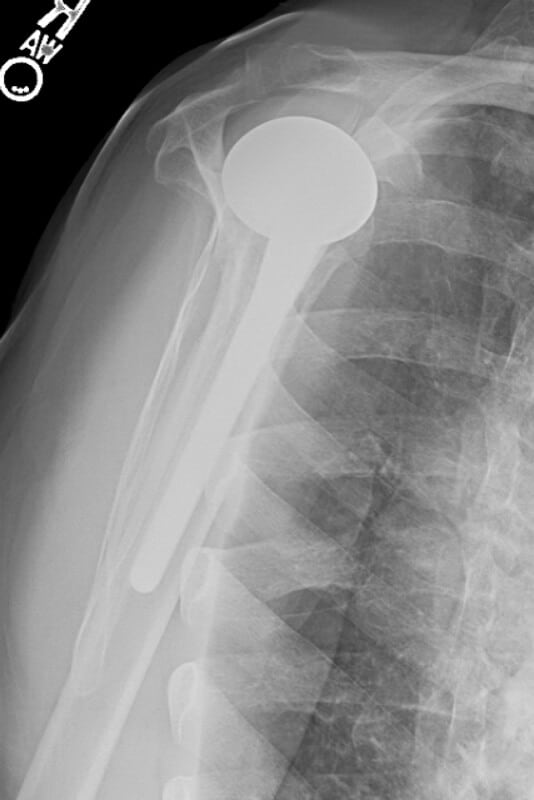

DePuy, Global AP